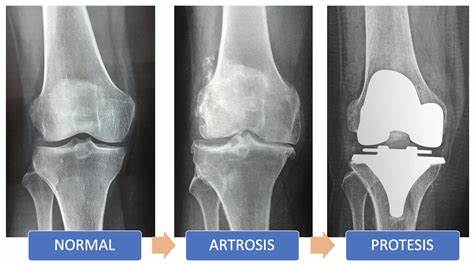

La rodilla es una articulación de carga, adaptada perfectamente a su función. Sin embargo, las sobrecargas persistentes o los movimientos repentinos o incontrolados pueden provocar diversos tipos de lesiones de las estructuras de esta región, determinados por las características anatómicas de la misma. De todas las articulaciones de carga, es la más vulnerable al traumatismo, accidental o repetitivo, en forma de uso y desgaste.

El desgaste es una enfermedad articular de la rodilla más común y está en relación a la carga que sufre esta articulación, es una afectación crónica, degenerativa y progresiva existiendo la degeneración, pérdida del cartílago y

alteración del hueso subcentral.

La gonartrosis es considerada una de las patologías que con mayor frecuencia ocasionan un impacto social, económico y sanitario importante. Representa un proceso degenerativo que puede afectar uno o más de los compartimentos que presenta esta articulación. La causa aún es desconocida. Se presenta en etapas tardías de la

vida y clínicamente se manifiesta con dolor, deformidad y limitación de la movilidad articular.